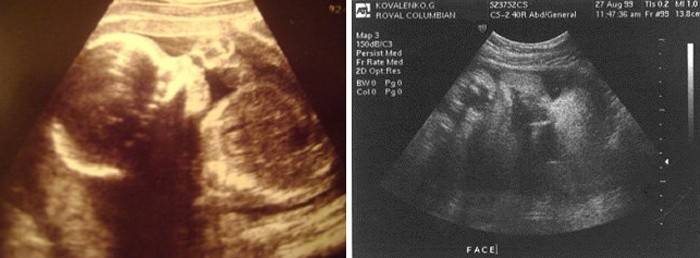

Por esta altura, o bebé cresceu - o seu peso é de cerca de 3600-3700 g, a altura pode atingir os 55 cm e esta será a principal dificuldade para o parto - quanto maior o bebé, mais difícil será passar pelo canal do parto. Aproximadamente 5% das crianças podem nascer neste período, geralmente as entregas passam antes desse período. Mas mesmo neste momento, o parto pode ir muito bem e os médicos muitas vezes apenas observam as mulheres grávidas sem recorrer à estimulação artificial do parto. As crianças nascidas neste período sentem-se bastante normais e desenvolvem-se ativamente, mas se não houver tendência para o nascimento precoce, serão prescritos hospitalizações, exames e preparação para o parto - será realizada uma ultrassonografia para avaliar as condições do feto, líquido amniótico e placenta, assim como o colo do útero. Mas normalmente a gravidez prossegue bastante favoravelmente até neste período e nenhuma intervenção se necessita, pode levar o bebê bastante seguramente. Ainda não há compactação dos ossos do crânio e deterioração grave com o envelhecimento da placenta, diminuição do líquido amniótico e ressecamento da pele do bebê e hipóxia fetal. Se isso for revelado durante o exame, a questão da estimulação imediata do processo de nascimento é resolvida.